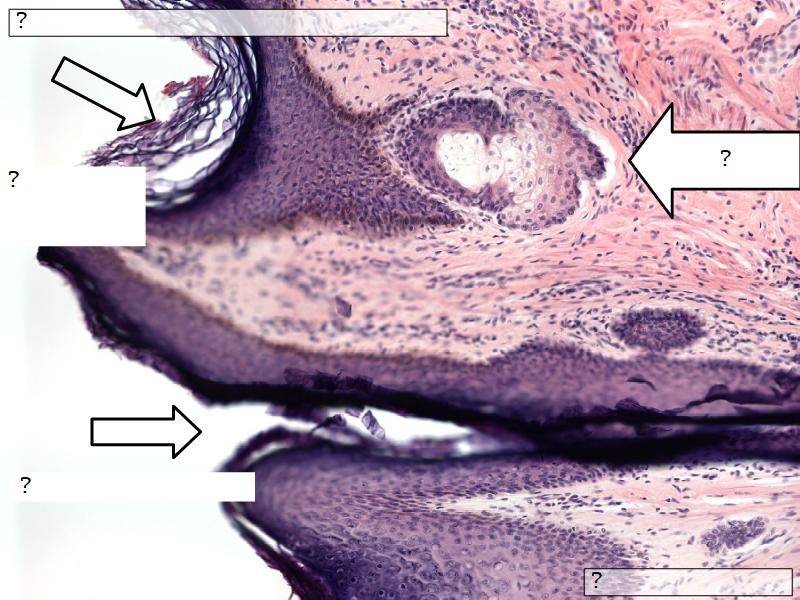

What are the main morphological features of the nipple?

(4)

Morphology

- Covered with skin

- Consists of dense collagenous connective tissue

- Interlaced with smooth muscle fibres

- Contains openings of lactiferous ducts

Skin

- Keratinized stratified squamous epithelium

- Sebaceous glands

Stroma

- Collagenous connective tissue

- Irregular dense connective tissue

- Smooth muscle

- Fibres and bundles

- Lactiferous sinusses

- Stratified cuboidal epithelium